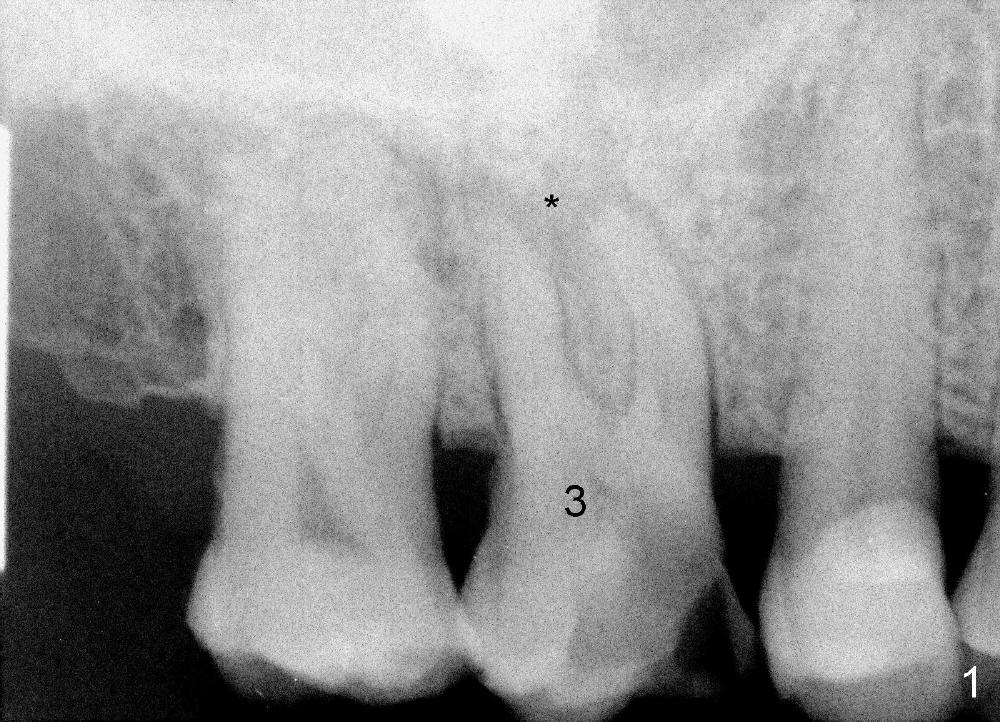

A 72-year-old man is a bruxer with #3 cusp fracture with chronic periapical radiolucency (Fig.1 *) and #4 acute crack.  It appears reasonable to take care of emergency (#4 extraction and immediate implant (Fig.3-7: 4.5x20 mm, 45 Ncm)) followed by root canal therapy or extraction for #3.  Eight (Fig.8) and 14 (Fig.9-11) days postop, the patient is doing fine and the wound heals normally.  But he does not agree any treatment for #3, since it is asymptomatic in spite of a fistula associated with the tooth (Fig.8,9 >).  Three months postop, the patient is still asymptomatic and is ready for #4 restoration since the tooth #28 cracks.  Follow-up PA shows the persistent distal gap (Fig.12 >, as compared to Fig.4), accompanied with crestal bone resorption (*).  Clinically the implant has mild mobility and light tenderness. The patient still refuses #3 treatment. It appears that the implant has failed to osteointegrate.  In brief, do not place an immediate implant next to active infection.